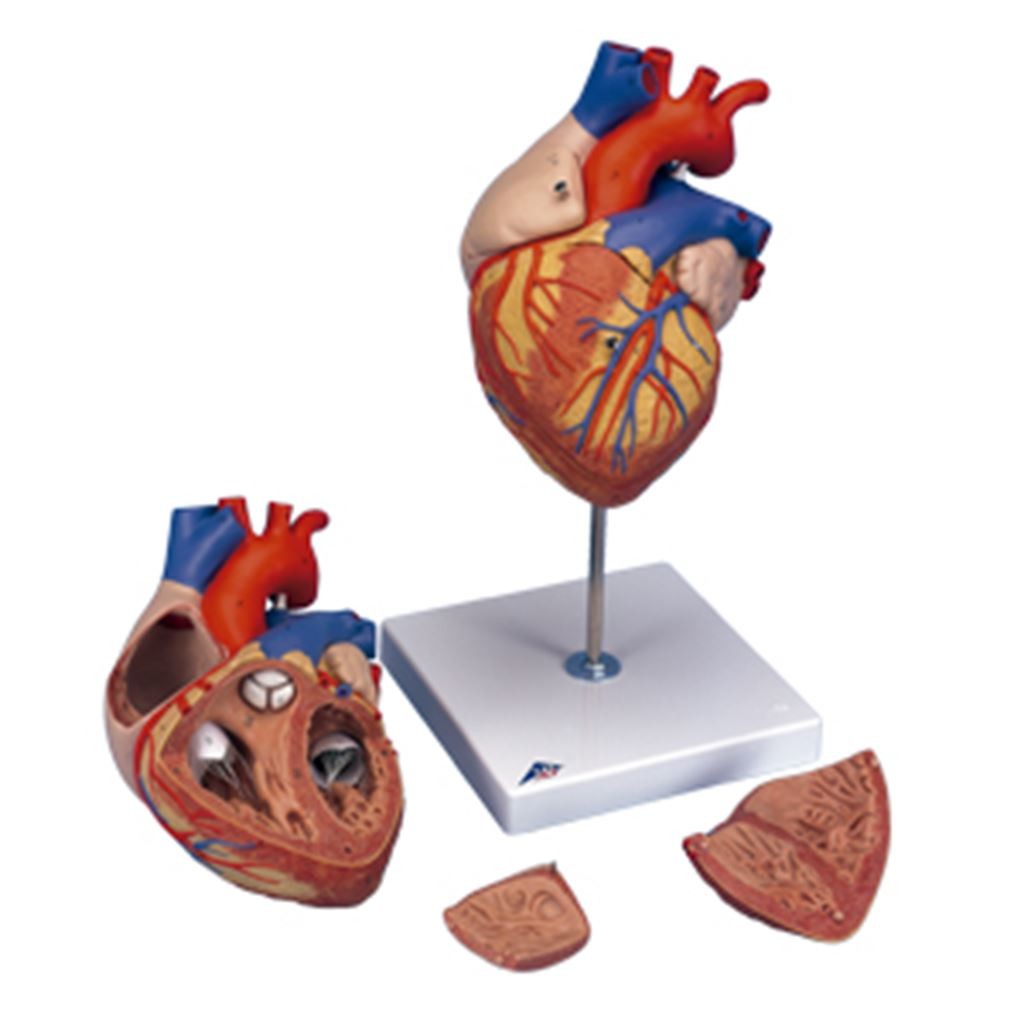

CORAZON MEDIANO

CORAZON MEDIANO

$1,566.00

CORAZON MEDIANO

CORAZON MEDIANO